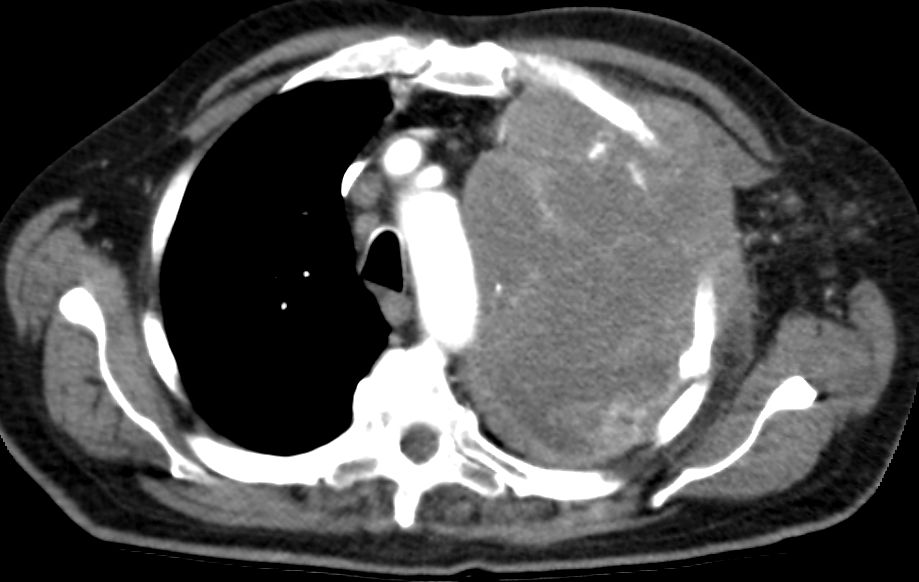

| Thoraxwanddestruktion | Plattenepithelkarzinom des rechten

Lungenoberlappens mit Destruktion der Thoraxwand und mediastinalen

Lymphknotenmetastasen. ![]() |